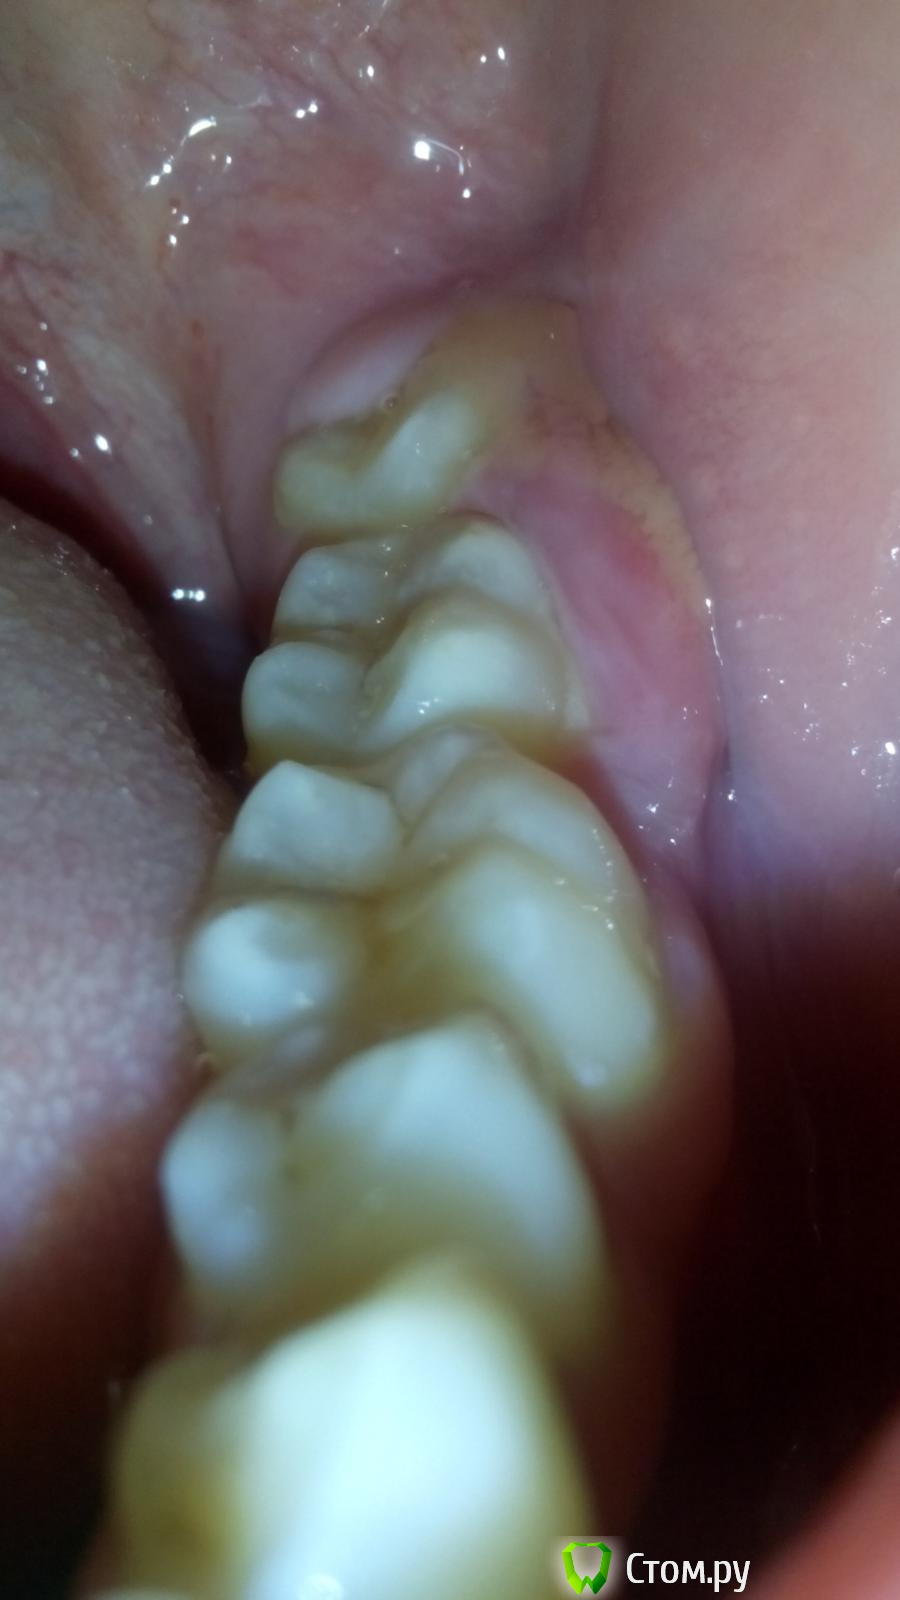

saadun Опубликовано 27 июня, 2014 Поделиться Опубликовано 27 июня, 2014 2-3 дня уже с воспалением хожу ночью болело, днём как будто и нет, надеялся, что поможет полоскание. Знаю что надо было сразу, завтра пойду к врачу, но хочется узнать что это ? Нервничаю, ещё пару часов назад начало болеть место воспаления. Ссылка на комментарий

Korel Опубликовано 28 июня, 2014 Поделиться Опубликовано 28 июня, 2014 но хочется узнать что это ? Перикоронарит Нервничаю Знаю что надо было сразу, завтра пойду к врач Раз знаете - делайте. Ссылка на комментарий